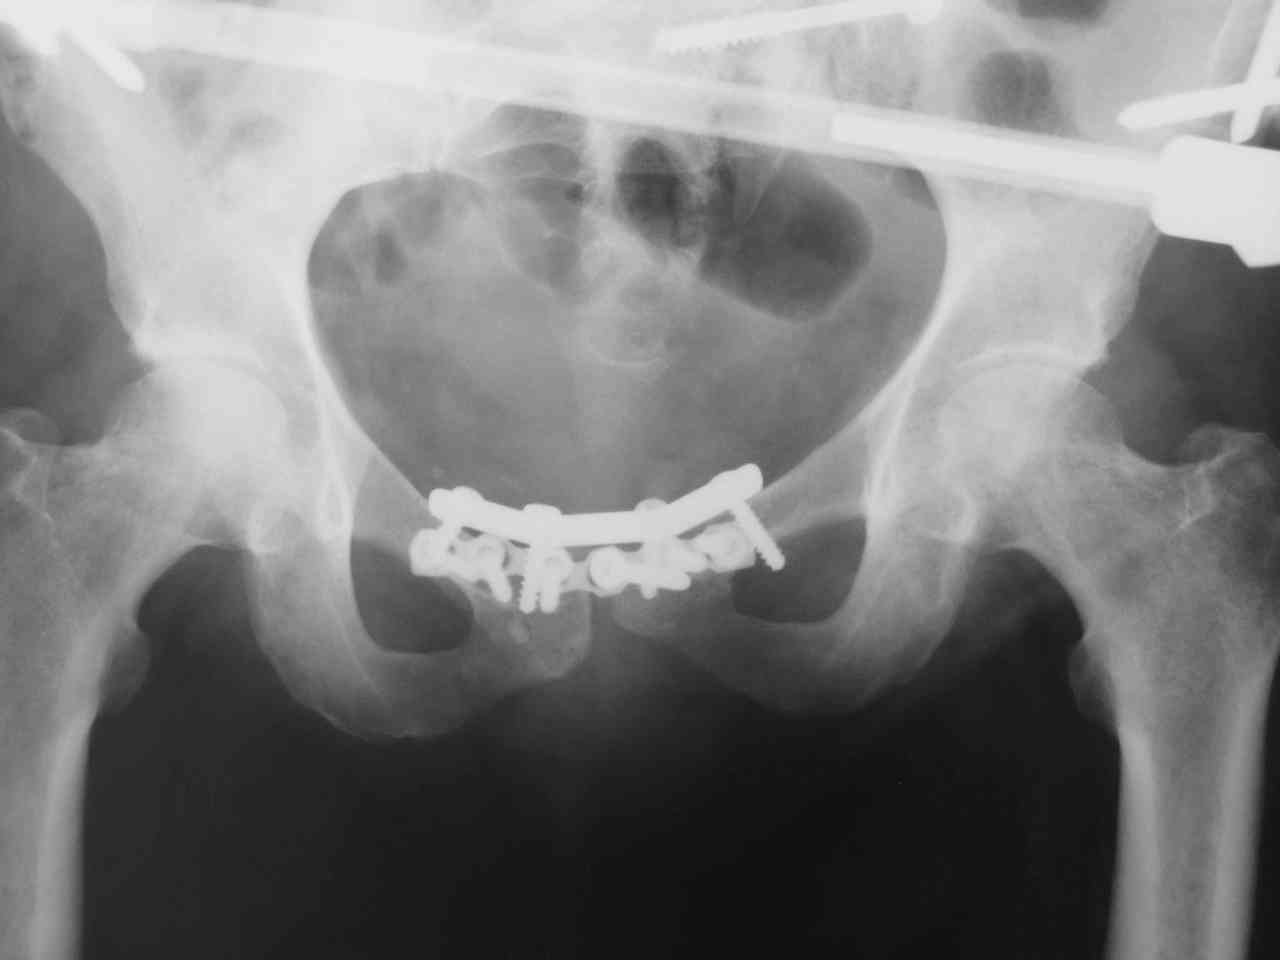

Пациентка получила травму таза 9 месяцев назад (перелом латеральной массы крестца слева, разрыв лонного сочленения).

Лечилась в стационаре другого города, без успеха. В мае 2007 прооперирована в нашем отделении, выполнена открытая репозиция повреждений, остеосинтез винтами латеральной массы крестца и пластинами лонного сочленения. Дополнительная фиксация аппаратом внешней фиксации. 3 недели спустя упала в палате на ягодицы, при этом получила повторную травму таза, смещение отломков. Уважаемые коллеги каково ваше мнение о способе фиксации полученных повреждений. С уважением Алексей.